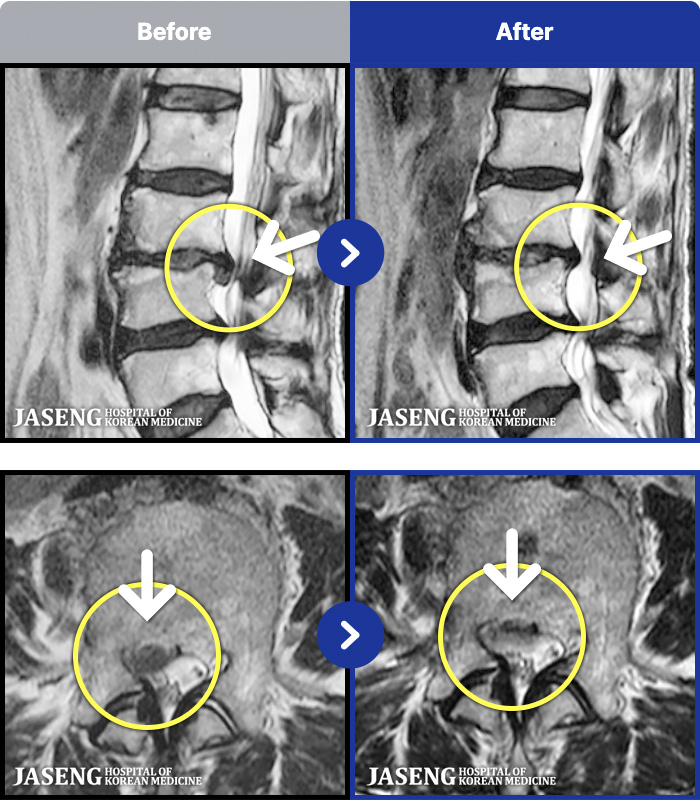

1,287 MRI ũ ʸ Ȯϼ.